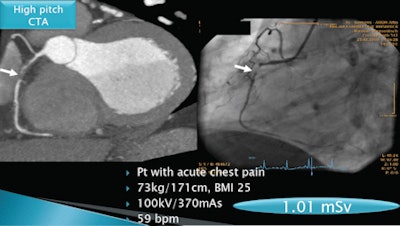

Austrian radiologists have found a way to cut the radiation dose of coronary CT angiography (CCTA) studies to as low as 1 mSv by using a high-pitch scanning protocol on a 128-slice scanner for patients with low heart rates.

Traditional retrospectively gated 64-slice coronary CTA is associated with relatively high radiation doses of approximately 12 mSv, but an emerging high-pitch CT angiography technique, performed on a 128-detector-row dual-source scanner, can reduce dose significantly, said Tobias DeZordo, MD, from the Medical University of Innsbruck. DeZordo presented his group's research on the subject at the 2010 RSNA meeting in Chicago.

DeZordo, along with lead researcher Gudrun Feuchtner, MD, and colleagues, acquired all images on a 128-detector-row dual-source CT scanner (Somatom Flash, Siemens Healthcare, Erlangen, Germany). The high-pitch Flash protocol uses a pitch setting of 3.4, prospective ECG synchronization, and a short scan time of only 0.3 seconds, he said.

Image quality of coronary arteries in coronary CTA was scored as "diagnostic" or "nondiagnostic" (per the American Heart Association's 16-segment classification). Radiation dose was estimated based on dose-length product, while contrast agent volume in CCTA was compared between the three techniques. Among the 103 patients, Flash high-pitch scans were acquired in 45% (n = 46), adaptive sequence in 37% (n = 39), and retrospective ECG gating in 8% (n = 19).

Among the total 67 coronary CTA studies, the triaged protocols included high-pitch Flash scans in 25% (n = 17), adaptive triggering in 52% (n = 35), and retrospective spiral scans in 22% (n = 15). The total mean dose for all protocols for the 67 studies was 4.8 mSv ± 4.7, DeZordo said, but mean doses for the protocols as well as the contrast dose varied, with significantly reduced dose and contrast utilization in the Flash scans.

In four patients (0.5%), high-pitch CTA had nondiagnostic image quality for at least one coronary artery (right circumflex artery, n = 4; circumflex, n = 1). In each of these patients, heart rates increased during the CT scan to higher than the 60 bpm threshold for optimal Flash scanning (captured heart beats: 60, 61, 61, and 63 bpm). When this occurred, a sequential (n = 3) or spiral (n = 1) exam was appended to ensure diagnostic image quality, DeZordo said. The total radiation exposure in these patients was a mean 3.9 mSv (representing the additional sequence) and 13.5 mSv (representing the additional spiral acquisition).

| Coronary artery stenosis is detected by coronary CTA (left) and conventional angiography (right) in a patient with acute chest pain. All images courtesy of Gudrun Feuchtner, MD. |

"High-pitch Flash mode scanning is reliable for coronary CTA if the heart rate is lower than 60 bpm, and high-pitch scanning allows for low radiation dose as well as [lower] contrast agent volume," DeZordo said. "High-pitch spiral mode can be integrated in clinical cardiac CT practice using our proposed triage, and permits a tenfold radiation dose savings and contrast volume savings."